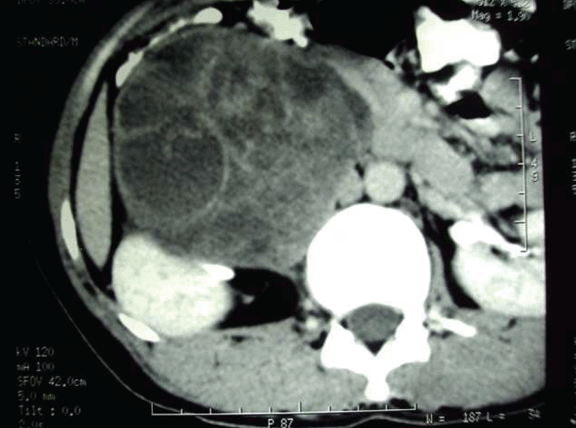

Computed tomography (CT) scan revealed a large well defined circumscribed oval complex cystic mass lesion in right hypochondrium and lumbar region abutting right lobe of liver and right kidney. (Figure 1)

Figure 1: Computed tomography scan showing retroperitoneal cyst with multiple septation may be hydatid cyst abutting liver.